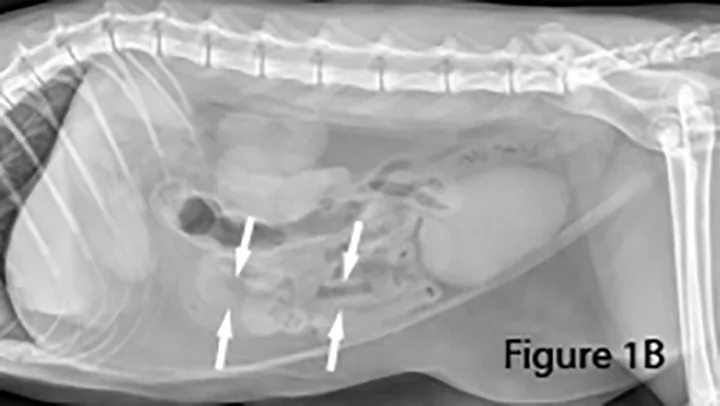

A foreign body (ie, rock) is identifiable in this canine small intestine. The markedly dilated segment of jejunum (arrows) leading up to the foreign body (~4× the height of L5) is significant.

Markedly gas-distended segment of jejunum (arrows) measuring ~2.2 cm in diameter is present ventral to the feces-filled colon (C) in this cat. The foreign body (arrow) appears as an abnormal, rectangular, heterogeneous radiolucent (gas) structure. Note the presence of normal bowel.